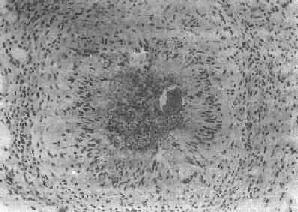

(2)慢性虫卵结节:急性虫卵结节经10余天后,虫卵内毛蚴死亡,坏死物质逐渐被吸收,虫卵破裂或钙化,其周围除类上皮细胞外,出现异物巨细胞和淋巴细胞,形态上似结核结节,故称为假结核结节(图19-7)。少数虫卵结节一开始即为假结核结节,而不经过急性虫卵结节阶段。最后,假结核结节中的类上皮细胞为纤维母细胞代替,并产生胶原纤维,使结节纤维化。其中央的卵壳碎片及钙化的死卵可长期存留。

血吸虫病之慢性虫卵结节

图19-7 血吸虫病之慢性虫卵结节

结节中央有破裂和钙化的虫卵,其周围有类上皮细胞和异物巨细胞,形成假结核结节